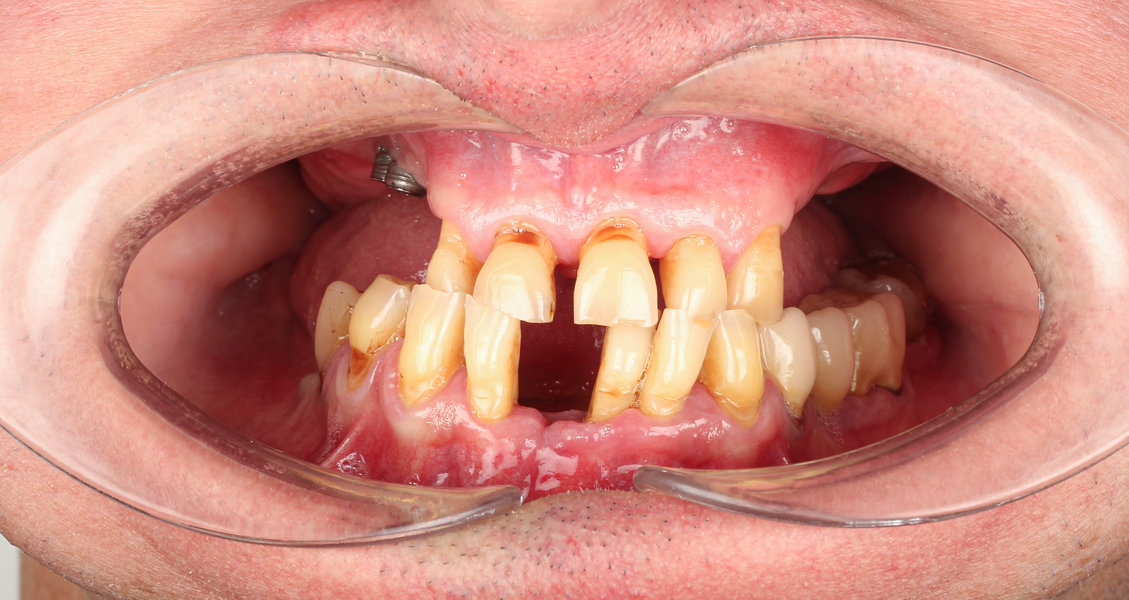

După inserarea unui implant dentar – o rădăcină artificială din titan sau zirconiu –, urmează etapa de protezare, adică atașarea unei structuri protetice (coroană, punte sau proteză) care înlocuiește dintele lipsă.

- Perioada de osteointegrare (3–6 luni)

- Amprentarea digitală sau clasică a zonei

- Persoane cu dinți lipsă parțial sau total

- Pacienți care nu se adaptează la protezele mobile

- Persoane cu pierderi osoase moderate (cu adiție osoasă, dacă este necesar)